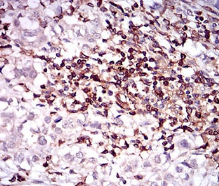

CD68 Mouse Monoclonal antibody[3F7D3]

IHC    1/200 - 1/1000